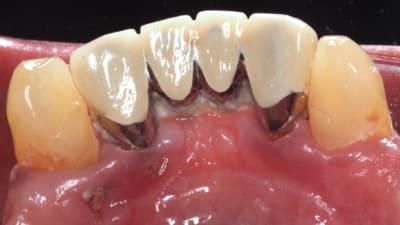

Case Reports Periodontics Repair of Lingual Gingival Fenestrations Through the Use of a Subepithelial Connective Tissue Graft By Elena Sanz-Miralles, DDS, Gary Greenstein, DDS, Joshua Shayefar, DMD, Robert N. Eskow, DMD September 01, 2020 11 min read